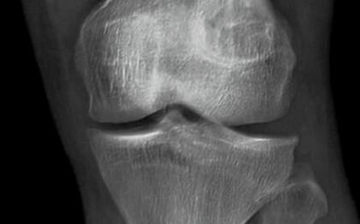

类风湿关节炎是一种以侵蚀性关节炎为士要表现的自身免疫性疾病。本病以女性多发,可能与遗传、细菌病毒感染、随机因素及性激素等方面有关,以慢性、对称性、多关节滑膜炎和关节外病变为主要临床表现,属于自身免疫件疾病。

类风湿关节炎误区,类风湿的8大误区 发病之初,患者可能只是因关节肿胀而导致双手在做穿针、系鞋带等精细动作时出现困难,随着疾病的发展,会慢慢变得无法完成简单的日常动作,如洗脸、穿农等。如果不爱时接受承坑的治疗,百分之五十和百分之七十的患者在患病两年后会出现骨质破坏,多数病人在患病3年后就会发生不同程度的残疾,严重影制生活质重。

(1)关节炎病理:关节炎为一种退行性病变,系由于增龄、肥胖、劳损、创伤、关节先天性异常、关节畸形等诸多因素引起的关节软骨退化损伤、关节边缘和软骨下骨反应性增生,又称骨关节病、退行性关节炎、老年性关节炎、肥大性关节炎等。